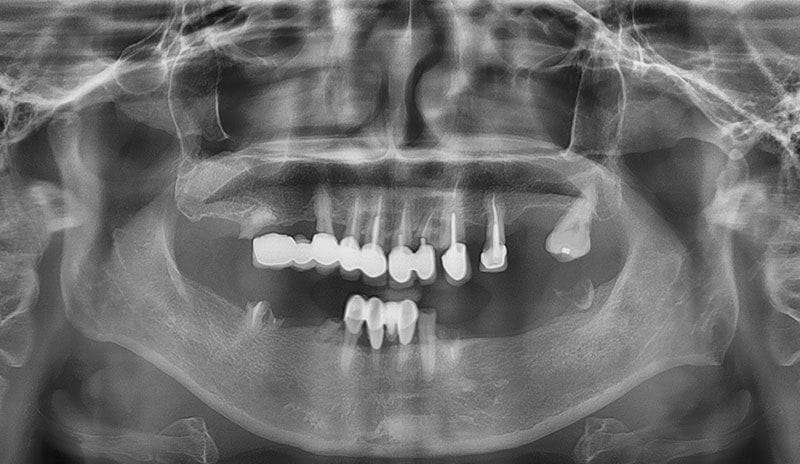

牙周病的症狀

通常牙周感染(牙周病)就像其他慢性感染一樣,是不會有明顯的疼痛症狀的,通常要等到較嚴重時,才會有明顯的不適,這就是牙周病的可怕之處。

牙周病症狀通常有以下幾點:

- 牙肉悶痛感

- 牙齦容易出血

- 牙齦紅腫

- 牙肉萎縮

- 牙齒對食物的敏感度提高(容易痠軟)

- 牙齒間隙越來越大

- 口臭

- 咬合位置改變,吃東西感覺不舒服

- 牙齒鬆動